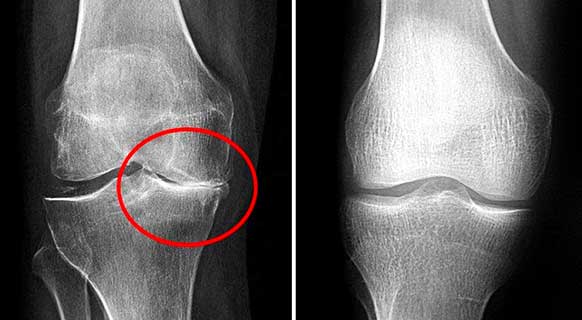

Foto rontgen sendi lutut sebelum dan sesudah mengonsumsi bubuk Invanil